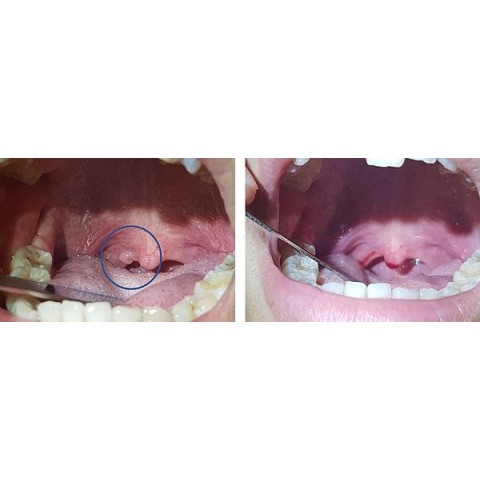

嘴巴裡面的小肉肉 ~ 乳突瘤

一位20出頭年輕美眉,到我的門診就醫,因為她被其他醫師告知,喉嚨裡面長了東西,希望能尋求幫助。 她很擔心,怎麼這麼年輕就得到腫瘤。經過詳細檢查,發現在她的懸壅垂(俗稱小舌或喉嚨滴ㄚ),有一個小小的腫塊,於是...